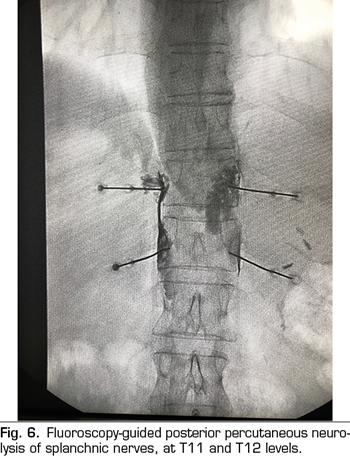

ENDOSCOPIC ULTRASOUND NEUROLYSIS OF THE CELIAC PLEXUS

Endoscopic ultrasound offers the advantage of larger visualization of the celiac plexus at a short proximity, allowing larger precision and safety in the administration of the neurolytic agent and avoiding injection into vascular structures through the use of Doppler (37) (Figure 5). However, the studies supporting endoscopic ultrasound neurolysis, considered similarly to percutaneous technique as a rescue therapy, are limited to retrospective uncontrolled studies (38). Pauli et al. published a meta-analysis that concludes that this technique achieves an 80% pain reduction in patients with pancreatic cancer (39). Some studies show a slight decrease in opioid consumption, but without strong scientific evidence.

Regarding adverse effects, they are reported in a limited series of retrospective publications and case series, being hypotension (11%), diarrhea (18%), and transient abdominal pain (1.5 to 8%) described (37). Theoretically, this technique is safer, with its anterior approach through the gastric wall and direct passage of the needle to the plexus visualizing the vessels, without having to cross the retrocrural space (41). Even so, fatal complications have also been published with this technique. Gimeno-García et al. (42) described the first complication of thrombosis and vasospasm of the celiac artery that produced a multiorganic ischemia and the death of the patient. Since then, this complication has been published in 2 other studies, which also ended in death (43,44). Other adverse effects described are retroperitoneal bleeding and 2 cases of paraplegia.

Among the contraindications related to this technique the following are found: the presence of gastric or esophageal varix - since they increase the risk of bleeding-, an unstructured anatomy, direct tumor invasion of the plexus, and congenital malformations of the celiac trunk or of the superior mesenteric artery.